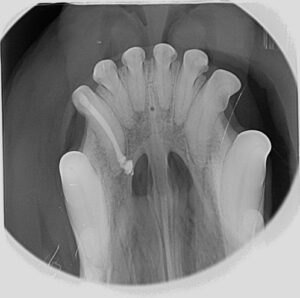

| 09:15-11:15 Uhr | Mikroanatomie und Pathophysiologie am verletzten Zahn |

| 14:00-15:00 Uhr | Praxis I Übungen am Hunde- und Katzenschädel – Zahnröntgen, Zugang zum Endodont, Pulpenexstirpation |

| 15:30-17:00 Uhr | Praxis II Übungen am Hunde- und Katzenschädel – Zahnröntgen, Zugang zum Endodont, Pulpenexstirpation Teil 1 |